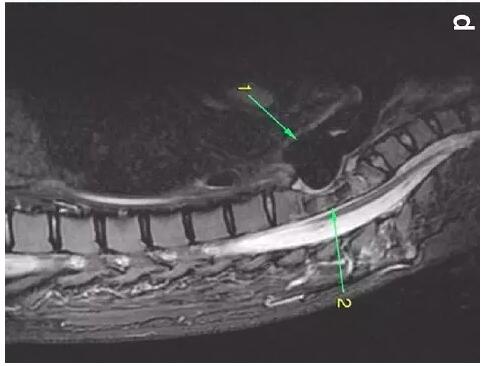

患者入住我院前行胸MRI已經(jīng)發(fā)現(xiàn)類似表現(xiàn)(圖d),當(dāng)時(shí)診斷為骨髓炎。

下圖箭頭1為氣切套管氣囊緊貼T1-4椎體水平,造成椎體前部受到侵蝕(箭頭2):

作者推測(cè)患者骨質(zhì)吸收、骨髓炎與氣切套管氣囊過度膨脹有關(guān),為氣囊過度膨脹造成椎體血流灌注降低所致。在我院住院期間,我們也發(fā)現(xiàn)高氣囊壓力才能防止漏氣。經(jīng)食道內(nèi)鏡檢查未發(fā)現(xiàn)氣管食管瘺。